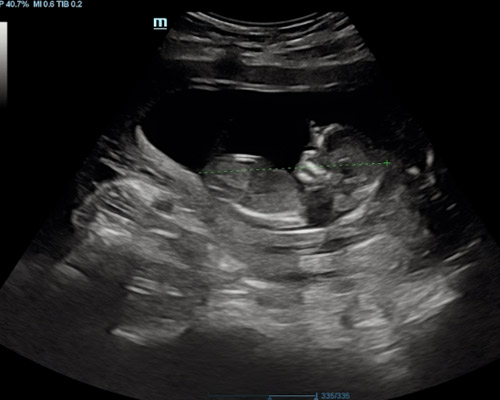

Typically carried out between 6 - 12 weeks, this scan uses ultrasound imaging to assess early development. It allows the sonographer to confirm that the pregnancy is located correctly, check for a heartbeat when visible, and measure the embryo to estimate how far along you are. It can also identify whether you are expecting more than one baby.

- Checking for single or multiple pregnancies

It can confirm the location of the pregnancy, check for a heartbeat, estimate gestational age and identify whether you are expecting more than one baby.